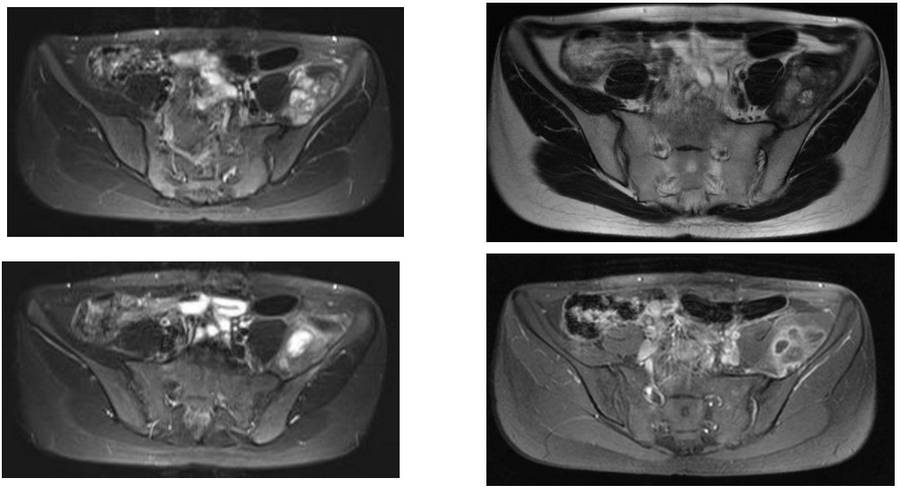

Ameliyat Öncesi: MR’da sol iliak kanat medialde düzensiz sınırlı, heterojen, periost reaksiyonunun eşlik ettiği tümör dokusu görülmekte